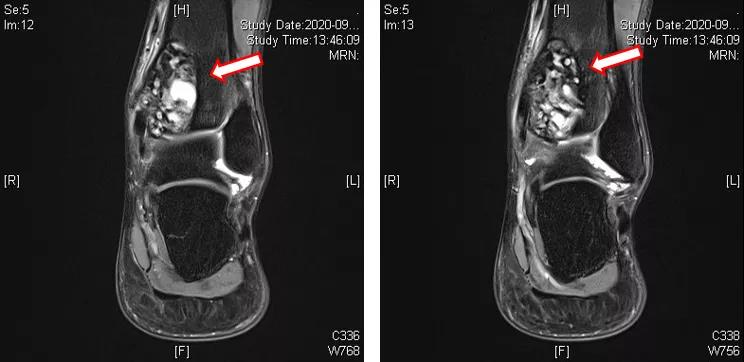

地舒单抗治疗后,复查左踝MRI提示:左侧胫骨内侧髁关节面下占位性病变,与2020-09-03 MRI对比,胫骨远端病变内T2WI高信号范围减小(图4~6)。

进一步完善CT检查提示:胫骨远端病变内不规则高密度影,成骨明显(图7~9)。

术前应用地舒单抗三次(120mg,ih,q1w),疗效显著,复查MRI提示胫骨远端病变内T2WI高信号范围减小;CT提示病变内不规则高密度影,成骨明显。

患者随后接受降期手术,同时术中探查见髓腔内灰白色肿瘤组织,质地较软,局部成骨硬化;术后病理显示肿瘤构成于短梭形细胞,成骨明显,新生骨小梁间见较密集的梭形细胞增生,未见确切多核巨细胞。